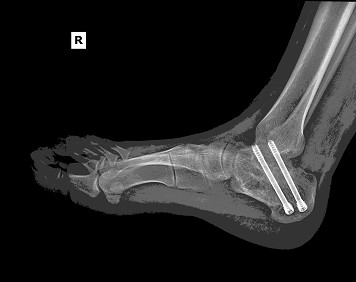

The patient underwent right subtalar arthrodesis with hardware removal at a local medical center. Intraoperatively, significant post-traumatic changes, joint degeneration, and residual deformity were observed. A structural bone graft was placed, and internal fixation was used to achieve stability. The procedure was successfully completed with minimal blood loss.

Follow-up X-rays: Confirmed hardware in situ with robust fusion progression.

Achieved stable joint fusion with no complications